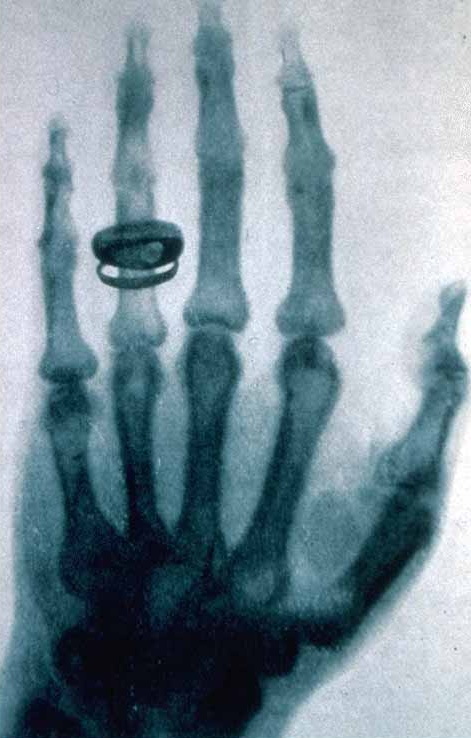

ویلهلم کنراد رونتگن فیزیکدان آلمانی و کاشف اشعه ایکس است که اولین جایزه نوبل فیزیک را در سال ۱۹۰۱ به دست آورد.

در 8 نوامبر 1895، ویلهلم کنراد رونتگن، در حالیکه مشغول تحقیق پیرامون خواص پرتو های کاتدی (همان الکترون ها) بود، به صورت کاملا اتفاقی، متوجه نوعی پرتو در لامپ کاتدی شد که آن را پرتوی مجهول یا پرتو x نامید که بعدها به یاد رونتگن، به آن پرتو رونتگن نیز گفته شد.

8 نوامبر مصادف با 17 آبان به یاد این دانشمند بزرگ روز رادیولوژی نام گرفته است.

تصویر دست همسر رونتگن در سال ۱۸۹۶ یکی از اولین تصاویر عکاسی شده به وسیله اشعه ایکس است.